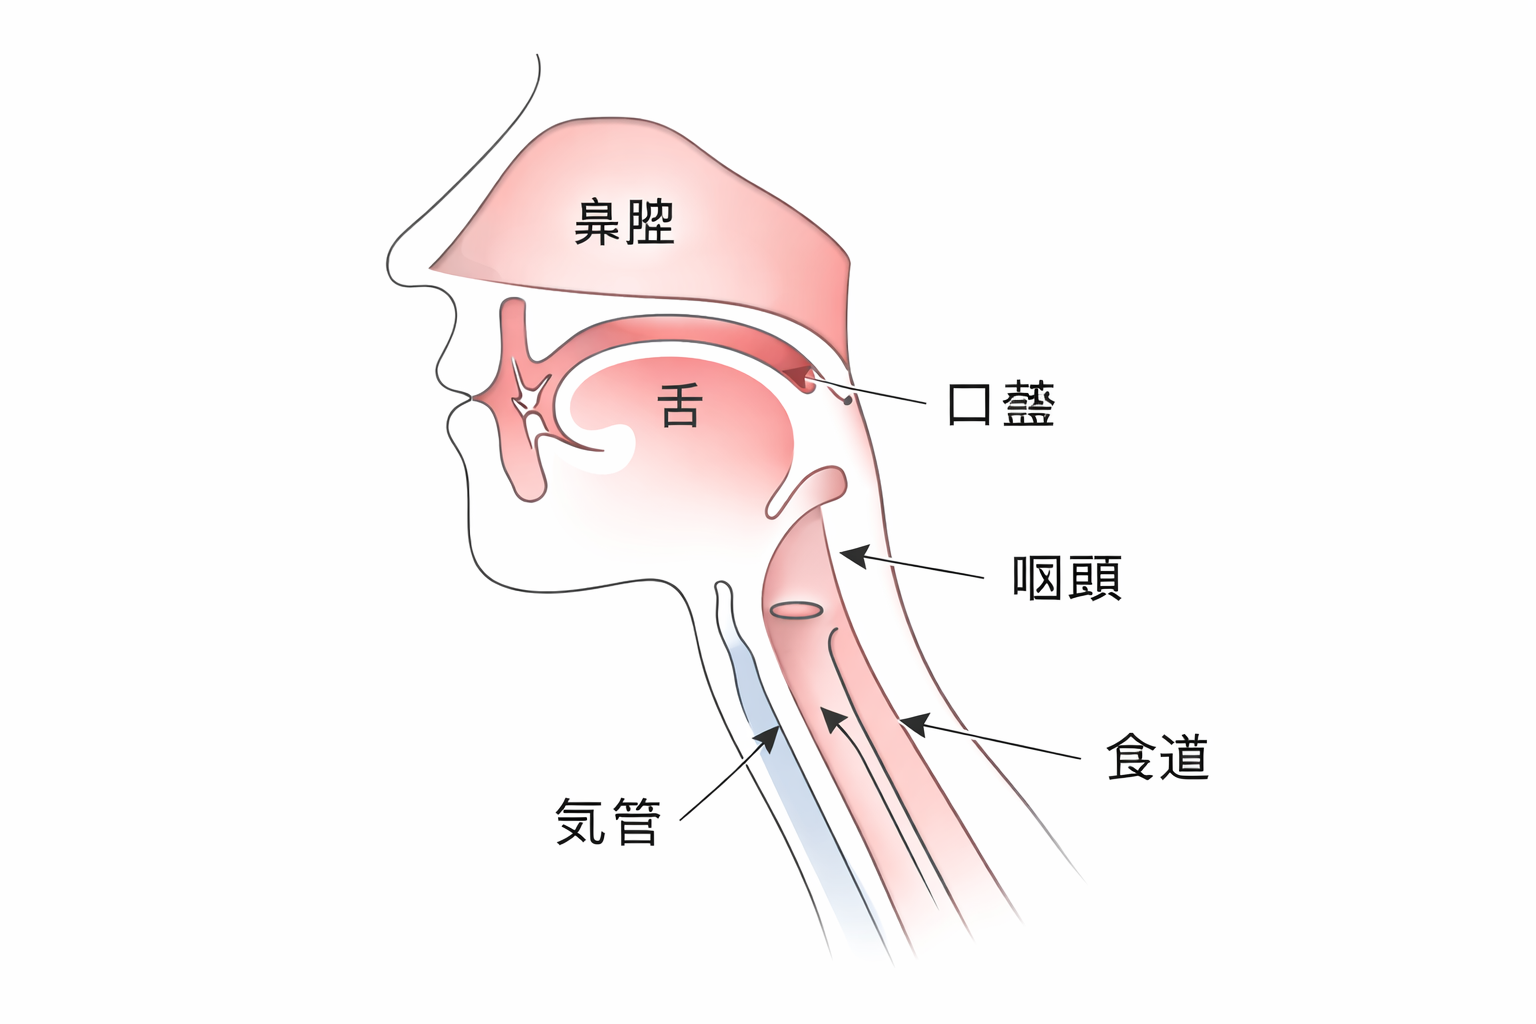

軟口蓋挙上装置とは

脳卒中などの後遺症で麻痺した口の奥の柔らかい部分(軟口蓋)を、押し上げる装置で、お口と鼻の間の空気漏れを抑えます。レジンと金属のバネでできており、上のあごに装着します。

脳卒中や神経疾患、頭頸部手術などにより、口の奥(軟口蓋)が麻痺したり、動きが弱まったりした方に適応されます。

麻痺などで動かなくなった軟口蓋を押し上げ、鼻への空気漏れを抑えます。

この装置の装着により、声がはっきりして会話がスムーズになる、食べ物の鼻への逆流を防ぐ、などの効果もあります。

スピーチエイドとは

スピーチエイドは、口と鼻の奥をうまく閉じられない「鼻咽腔閉鎖機能不全」を補い、発音や食事をスムーズにするための装置です。入れ歯や矯正装置の後ろに突起状のバルブが付いており、上あごに装着して使用します。装置の先端には、バルブという突起状の膨らみがあり、これが喉の奥の隙間をふさぐ役割をします。これにより、話すときに鼻から息が漏れるのを防ぎ、言葉がはっきりと相手に伝わりやすくなります。また、飲み物が鼻に逆流するのを抑える効果もあります。

鼻で息をする時には、喉の奥と鼻は空気が通る状態になっていますが、発音を行ったり、食べ物を飲み込んだりするときは、鼻に逆流しないように、鼻と喉の奥をふさぐ(鼻咽腔閉鎖といいます)必要があります。この機能を果たしているのが「軟口蓋」ですが、この組織の大きさが生まれつき足りなかったり、腫瘍の手術などで失った場合に、その足りない部分を補うことを目的とする装置です。